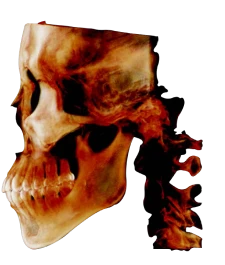

RAYSCAN 18х16 может с лёгкостью и точностью охватить обширную область анатомии. Его замечательная способность захватывать как назион, так и глабеллу, область от подбородка до лба, всё это в одном сканировании высотой 16 см действительно впечатляет.

Познакомьтесь с технологией получения изображений с использованием полноразмерного датчика от RAY. Этот метод не только позволяет получать объёмные изображения без сшивания, но и сводит к минимуму радиационное облучение в целях безопасности пациентов.

Ортодонтия & ЧЛХ

- Оценка роста

- Анализ симметрии лица

- План ортодонтического лечения

- Анализ дыхательных путей и ВНЧС

- Моделирование ортогнатической хирургии